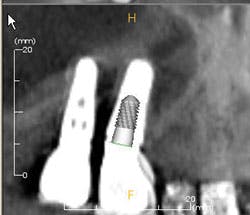

Figures 3a-b: Threads clearly in focus and CBCT (courtesy of Jeff Carlson, CDT, and Dr. R. Horowitz).

For one to four implants, take a vertical bitewing or periapical film. For five or more implants, take individual periapical radiographs, panoramic film, or a three-dimensional radiograph (cone beam computed tomography-CBCT scan). Line up the diagnostic radiograph of the implant correctly, with all indentations of the implant and the threads clearly in focus4,8 (Figure 3a-b).